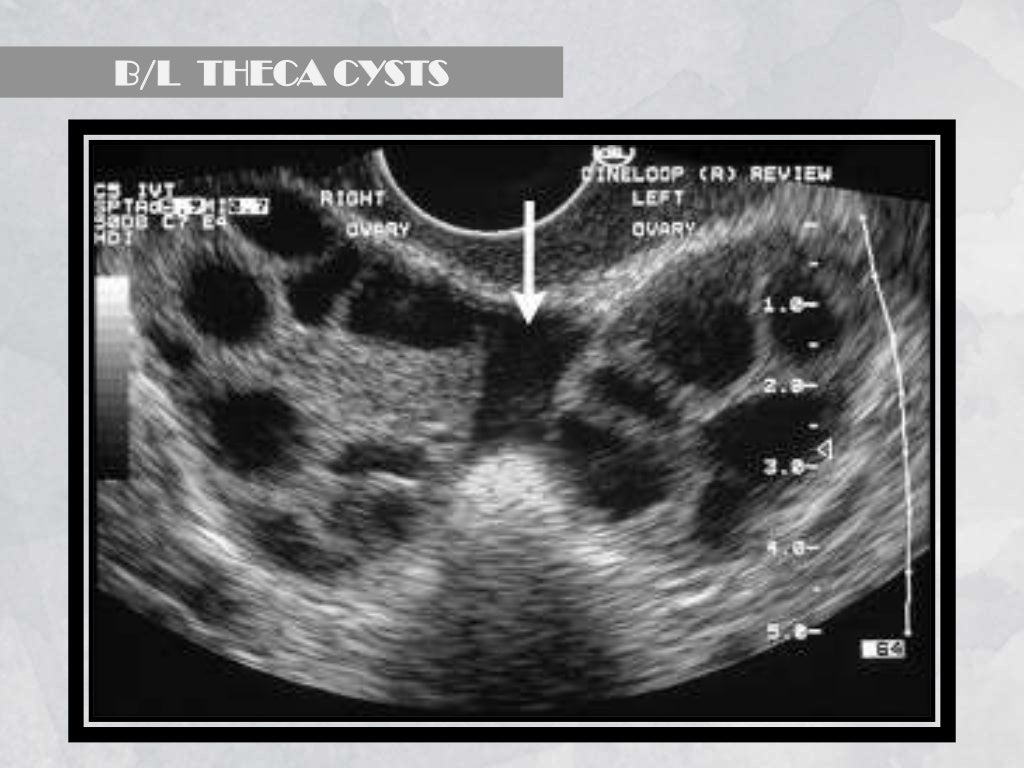

From www.slideshare.net

Imaging in obstetrics & gynaecology (part 1 Gynaecological scans in Imaging Techniques In Gynaecology In this article, the various types of imaging available will be discussed, with particular emphasis on their relative advantages and disadvantages. this article provides an overview of the contribution of ultrasound examination to the evaluation of gynaecological conditions by summarizing the basic physics of ultrasound, and ultrasound features. the role of imaging in the management of a wide. Imaging Techniques In Gynaecology.